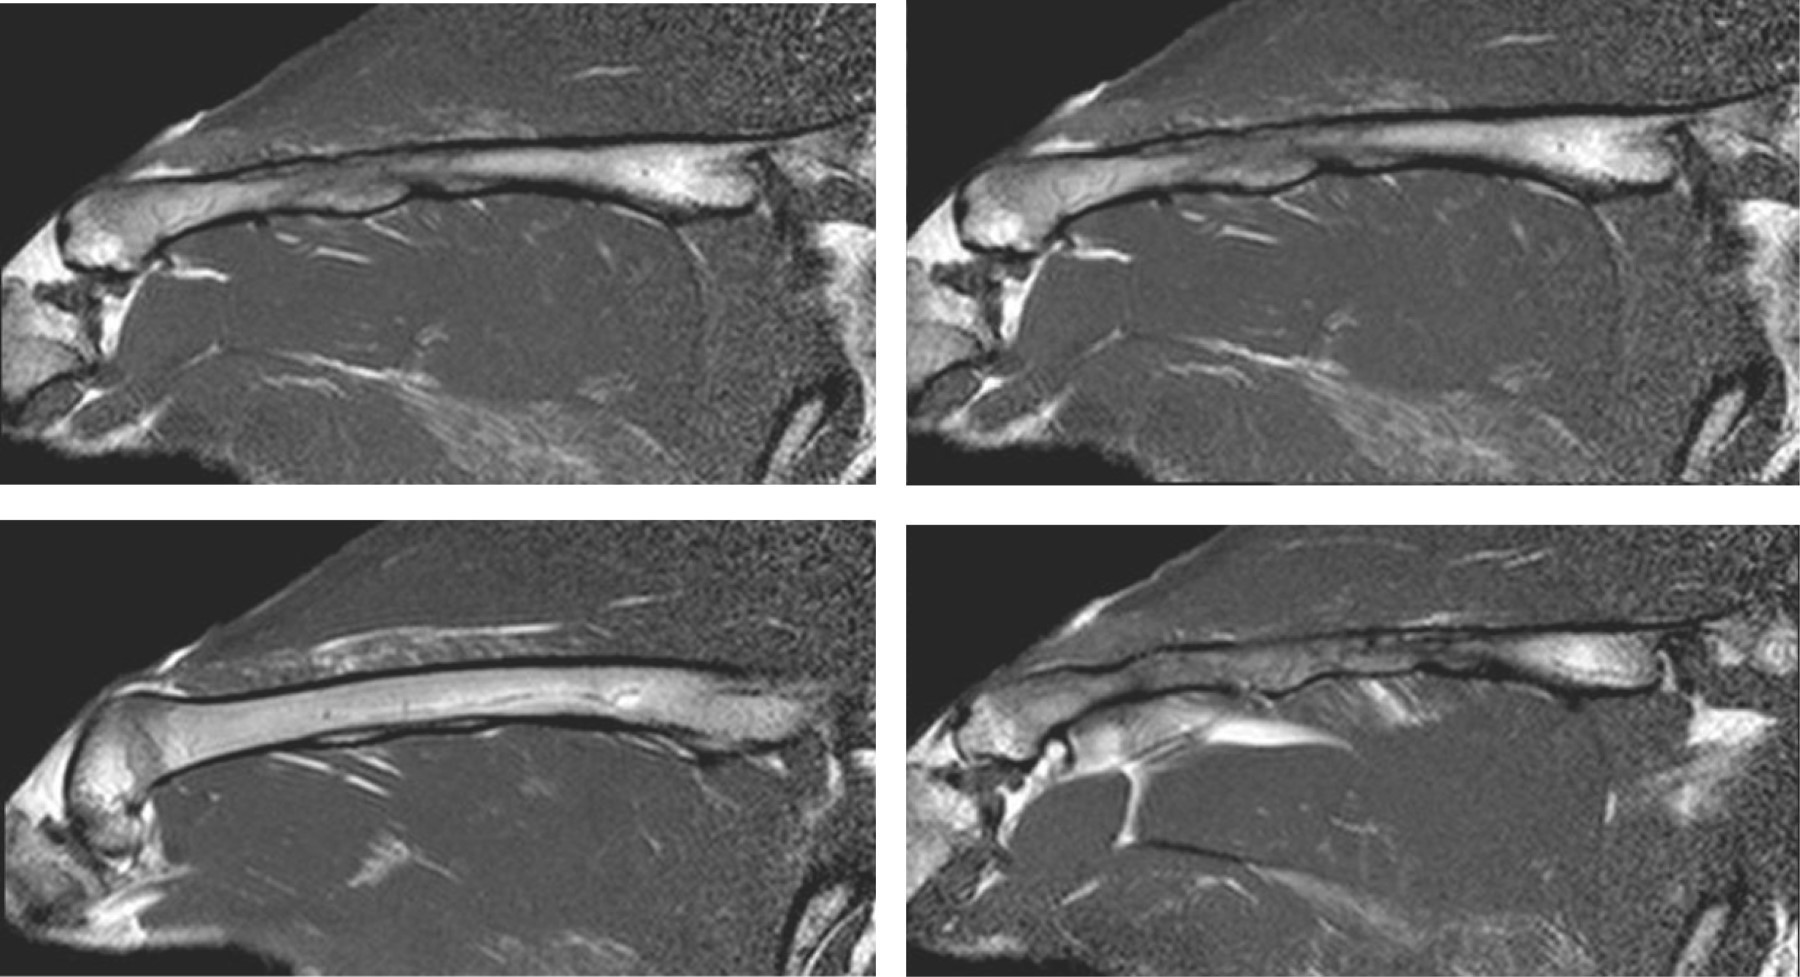

A los cuatro meses del procedimiento quirúrgico, todos los conejos fueron sacrificados y se les realizó estudios de imágenes: radiografías de ambos fémures, resonancia magnética y tomografía computarizada del fémur derecho de cada conejo. Las radiografías de ambos fémures se utilizaron para hacer una evaluación comparativa respecto al fémur sano (Figura 4). La resonancia magnética y tomografía brindaron datos para determinar la integración y/o reabsorción ósea (Figuras 5 y 6). Dichos estudios fueron evaluados por un médico especialista en diagnóstico por imágenes, subespecialista en el sistema musculoesquelético. El observador fue ciego al tipo de tratamiento.

Al evaluar la revascularización ósea a través de las distintas técnicas de imágenes se observó que en el grupo 2 (aloinjerto intramedular), todos los casos mostraron una revascularización completa (Figura 10), ya sea con la radiografía (RX), la resonancia magnética (RMN) o la tomografía computarizada (TC). Pudimos objetivar dichos hallazgos debido a la importante integración que se generó con este tipo de tratamiento, ya que radiológica y tomográficamente no encontramos diferencias en el hueso tratado con el contralateral. En cuanto a la resonancia magnética, vemos que todo el fémur presenta la misma señal tanto en secuencias T1 como densidad protónica con supresión grasa. Creemos que esto está dado por la integración y revascularización que se produce con este tipo de injerto. En el grupo 1 (aloinjerto extramedular) se detectaron conejos con una revascularización parcial entre cuatro y seis de los 10 conejos, según la técnica de imagen. La diferencia entre grupos fue estadísticamente significativa en el caso de la RX y TC, con un valor de p < 0.05. Cabe señalar que con la TC en las parciales se detectó un porcentaje promedio de revascularización de 82.5%.